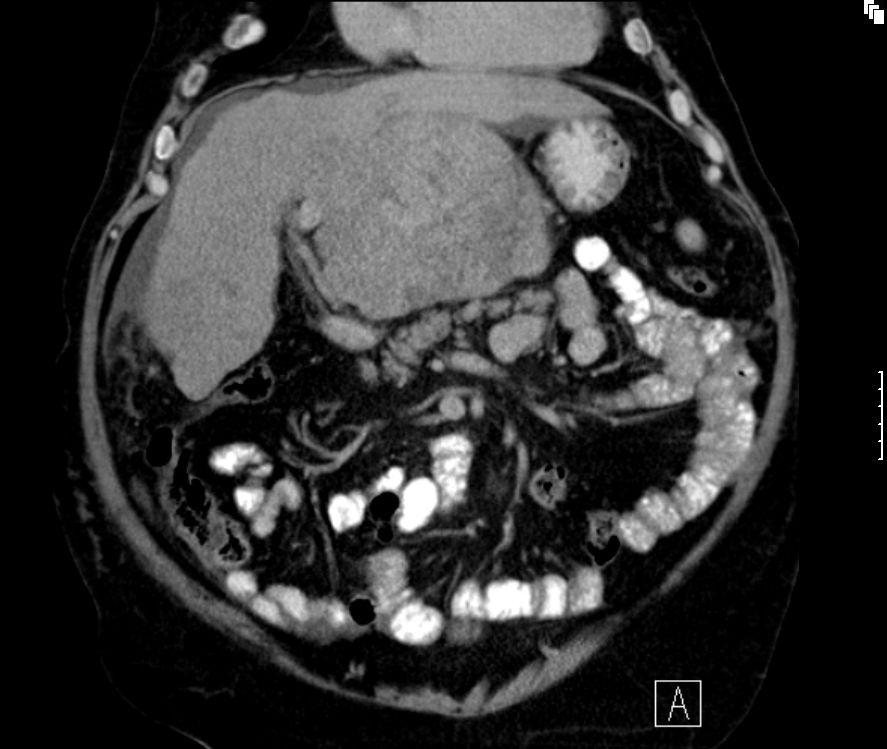

Sonographie, CT, MRT. typisch: AFP erhöht. Beispiele bildgebender Diagnostik